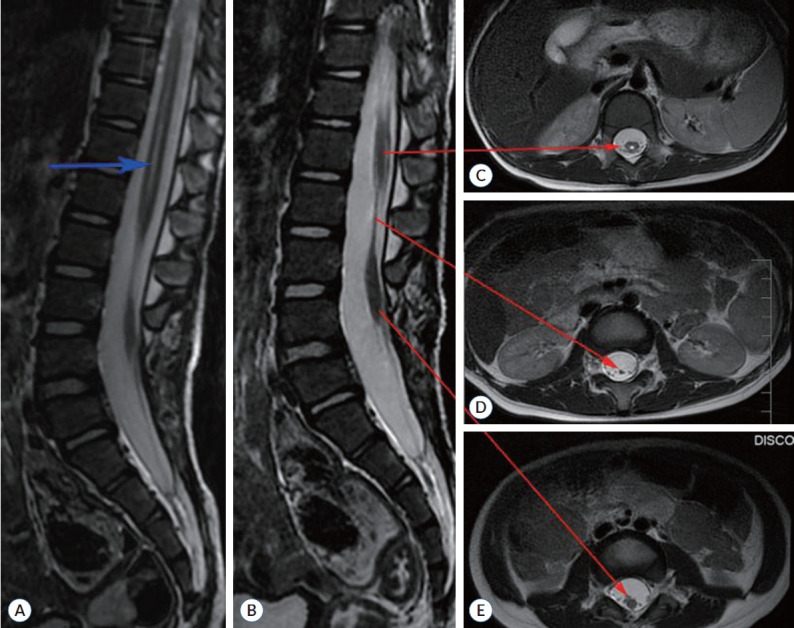

Abstract Image